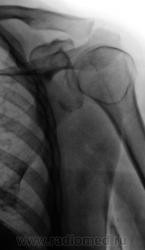

Аналогичное, только несколько в другой плоскости.

1.Neskolko_analogichnoe.JPG2._Neskolko_analogichnoe..jpg

В данном случае несколько слерозирован малый бугорок.

1. На двух левых снимках, то, что могло показаться "кистой" - желтые стрелки, действительно, как отметил Анатолий Владимирович, конечно никакая не киста, и укладка в данном случае "не виновата". Просто, головка в результате подвывиха олказалась несколько ротированной, что и поменяло "привычную картину". Мы довольно часть встречаемся с таким феноменом при подвывихах головки плечевой кости.

2. Конечно, пациент, в присутствии врача хирурга был взят за экран. В принципе все вопросы были решены, но коллега попросил сделать снимок " с поворотом" - это два правые снимка.

В том-то и дело, Валентин Львович, что если на двух левых снимках, выполненых при ротации плеча вследствии подвывиха, головка плечевой кости находится в ортогональной проекции и на снимке дает известный скиалогический эффект в виде кольцевидной склерозированой тени и разрежения структуры (такой же эффект на двух правых снимках в виде разрежения структуры в зоне большого бугорка), то на двух правых снимках, которые проекционно ближе к стандарту (большой бугорок практически на контуре) отмеченого мной разрежения структуры в норме быть не должно. Поэтому, очень рекомендую МРТ, КТ, хотя бы "возьмите пациента на конроль"